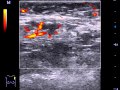

Диагностика рака молочной железы включает в себя совокупность современных методов и исследований. При планировании точной программы исследования необходимо учитывать особенности пациента и течение конкретного заболевания. Это первый этап, пропустить который просто невозможно. Врач проводит первичный осмотр молочных желез, узнает историю развития заболевания и общий анамнез.